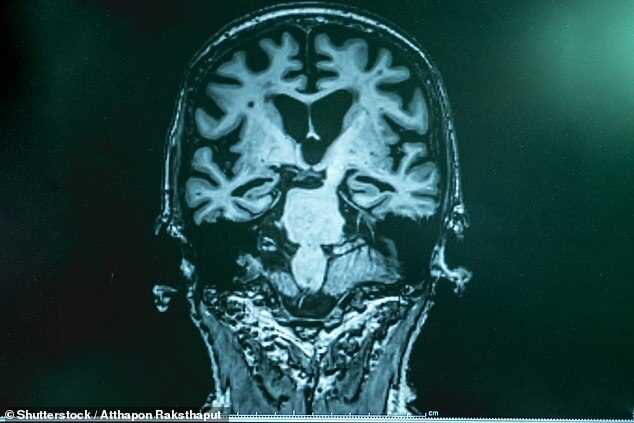

Ученые обнаружили, что для восстановления мыслительных способностей людей старше 60 лет требуется слабый электрический ток. Считается, что крошечные электрические импульсы синхронизируют их мозговые волны, чтобы мозг мог более эффективно работать.

Доктор Роберт Рейнхарт из Бостонского университета, который проводил исследование, сказал, что данные результаты важны, потому что они дают нам новое понимание основ работы мозга для улучшения памяти, а также для понимания возрастных изменений в мыслительном органе. Рейнхард говорит, что негативные возрастные изменения не являются неизменными, есть возможность вернуть прежнюю функцию кратковременной памяти, расстройство которой наблюдается при болезни Альцгеймера.